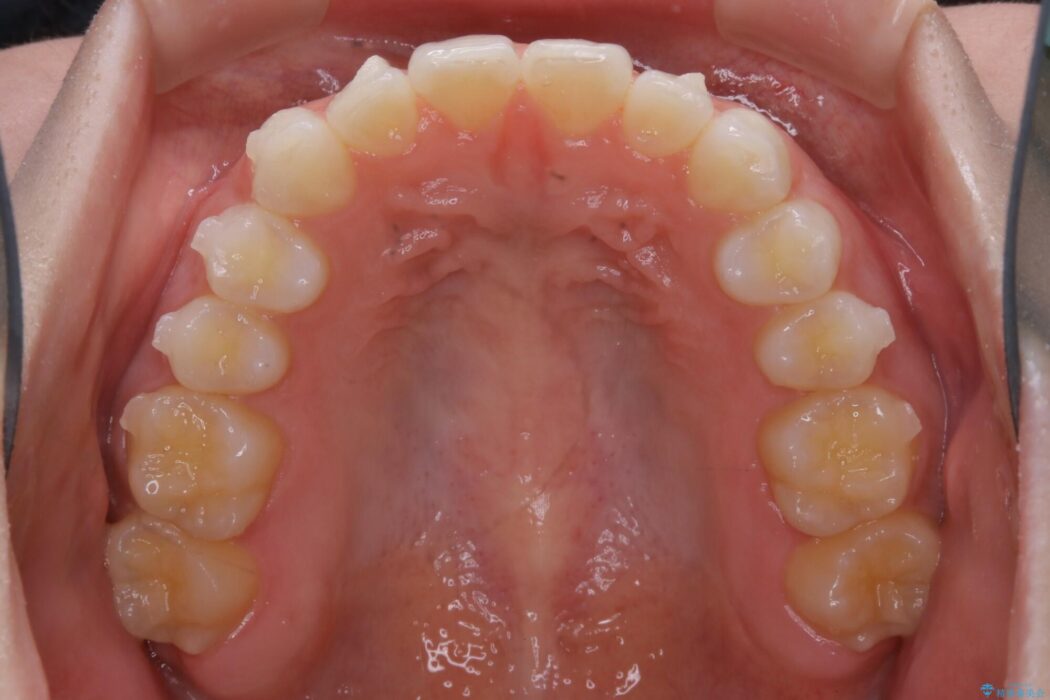

上下前歯のねじれなどで生じている歯列のガタつきをなおしたいとのことで来院されました。

精密検査をしたところ、奥歯に大きな問題がないため移動はほとんど必要がなく、また主訴であるガタつきの改善に必要なスペースも少量であったため、インビザラインのライトパッケージの治療をご提案しました。

半年という短期間でスピード治療が完了しました。